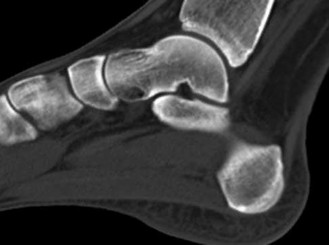

A 30-year-old female sustains a midfoot injury after falling from a horse. Radiographs demonstrate diastasis between the bases of the 1st and 2nd metatarsals. In a normal anatomic state, the native Lisfranc ligament originates and inserts on which two bony structures?

Correct Answer: Lateral aspect of the medial cuneiform to the medial aspect of the base of the 2nd metatarsal

Explanation:

The Lisfranc ligament is a stout, obliquely oriented intra-articular ligament that acts as the primary stabilizer of the second tarsometatarsal joint complex. It connects the lateral aspect of the medial cuneiform to the medial aspect of the base of the second metatarsal. Importantly, there is no direct ligamentous connection between the bases of the first and second metatarsals.